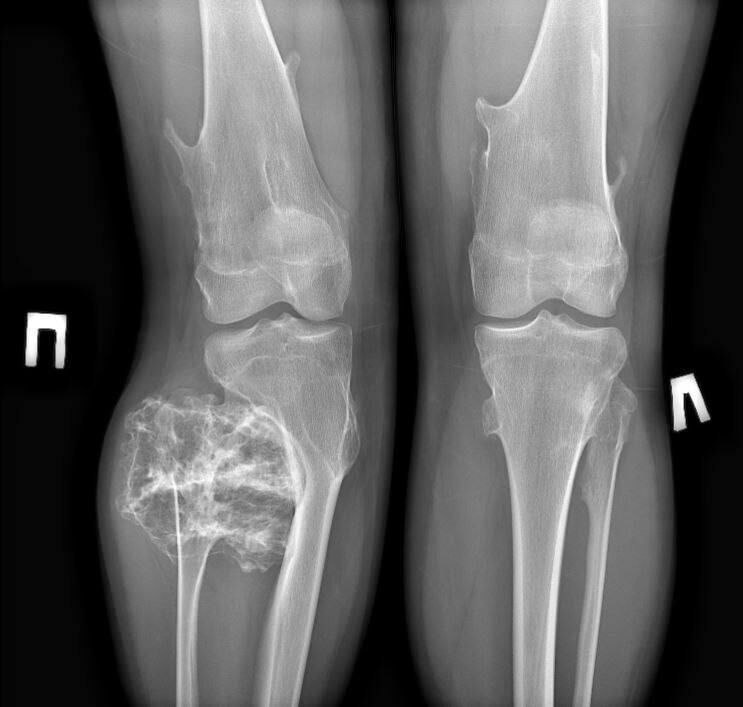

Твердое новообразование в области малоберцовой кости послужило поводом для обращения 15-летнего юноши с родителями в Московскую областную детскую клиническую травматолого-ортопедическую больницу.

В ходе обследования врачи поставили диагноз — остеохондрома. Это доброкачественное костное новообразование, вырост на поверхности кости, состоящий из костной ткани, покрытой хрящевой «шапочкой», и чаще всего возникающий в детстве и подростковом возрасте. Его размеры достигали 9х8х8 см. Специалисты приняли решение о плановом хирургическом лечении.

В ходе операции врачи успешно удалили опухолевидное образование в пределах здоровой костной ткани. После лечения пациента выписали домой на амбулаторное лечение по месту

жительства. Функция ноги сохранена в 100% объеме. Через 3 недели реабилитации он сможет вернуться к привычному образу жизни.